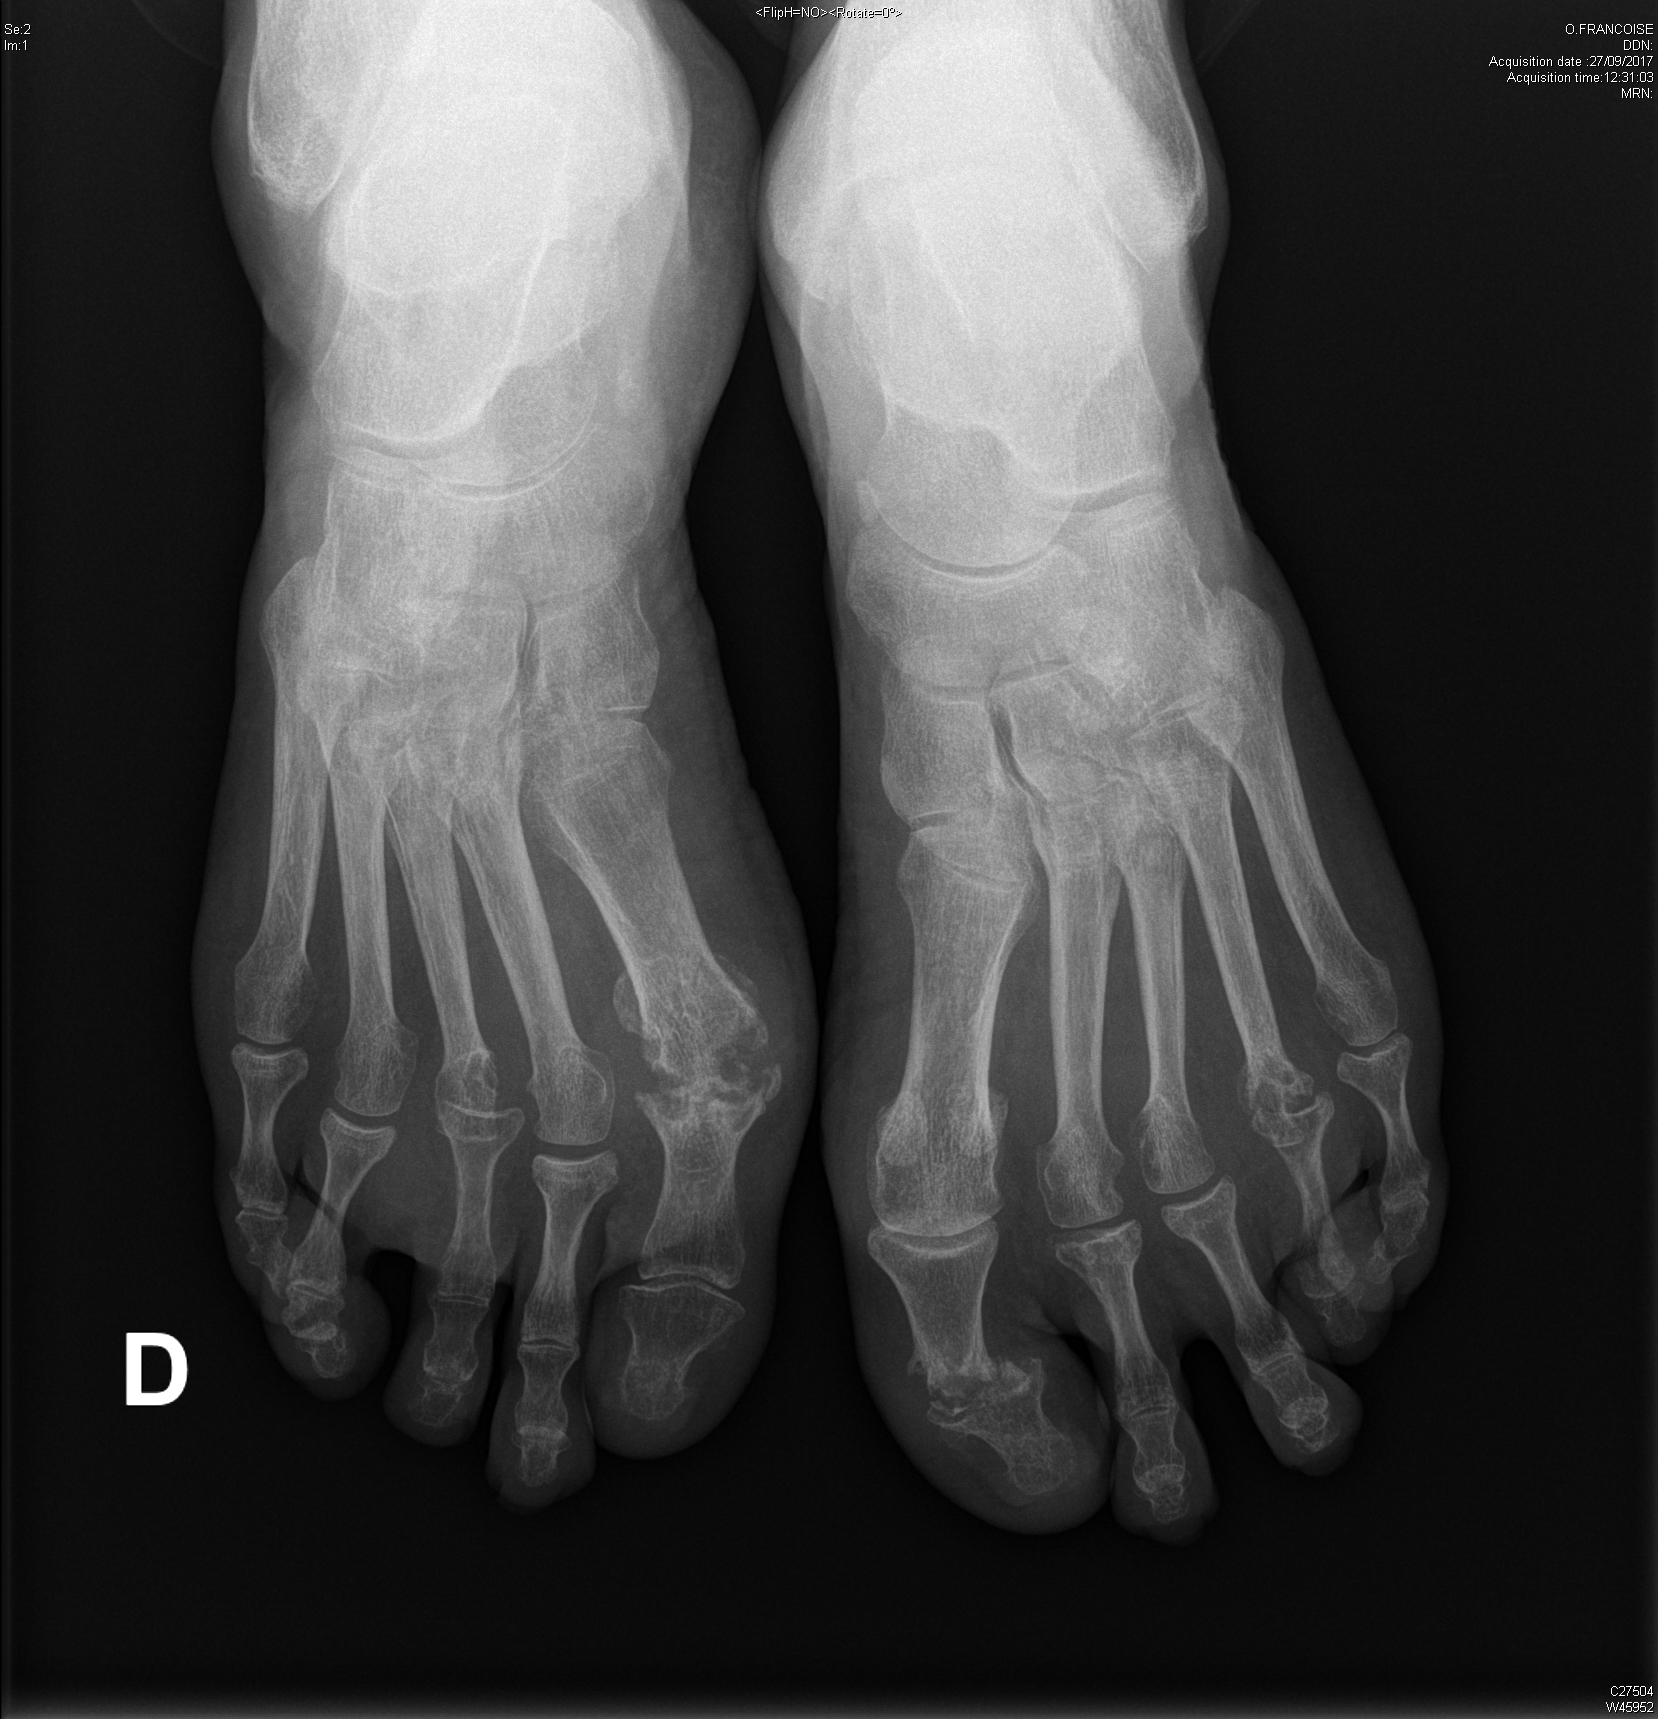

Polyarthrite rhumatoïde séropositive, sévèrement érosive aux pieds